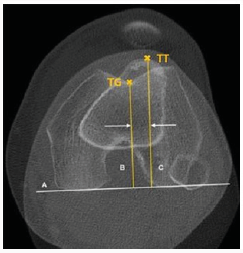

TThe mediolateral distance of tibial tuberosity and trochlea groove (TT-TG) is considered the gold standard for patellofemoral pain syndrome (PFPS) to determine lateral shift of tibia and femur [1]. Goutallier et al. [2] described TT-TG for the first time in radiological images. In 1994, a study by Déjour et al. [3] has shown a normal TT- TG range of 12.7 ± 3.4 mm using superimposed tomographic slice images. More than 20 mm are considered pathological. Tomographic image data of tibial tuberosity and trochlea groove are captured and superimposed in transverse plane (Figure 1) [4].

For calculation, two auxiliary lines were con- structed in the superimposition which are perpendicular to the tangent of posterior femur condyles (Figure 1). While one line starts at the lowest point of the trochlea (Figure 1), the other one runs through tibial tuberosity (Figure 1). The distance between the parallel lines describes TT-TG. Apart from radiation exposure in X-rays and expenditure of time for MRI, both procedures are expensive and elaborate. Therefore, there is a need to replace evaluation of TT-TG by another method. A measuring system based on navigated ultrasound is described which detects bony land- marks and sets them in relation. Implementation of navigated ultrasound as measuring method and imaging in one opens innovative possibilities to re-interpret value of TT-TG and improve its evaluation regarding PFPS.